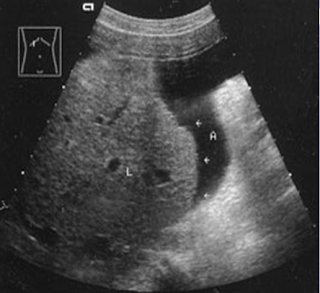

What is the sonographic appearance of Cirrhosis?

Hepatomegaly

Increased echogenicity and attenuation

Size

decrease of right lobe

Size increase of left and caudate

lobe

Nodularity

Fibrosis

Hepatospenomegaly

Ascites

Portal

hypertension

Hepatoma tumors

caudate lobe may be spared

What is Cirrhosis?

A chronic degenerative disease in which there is parenchymal necrosis, regeneration and fibrous tissue resulting in disorganization of lobular architecture. Lobules are infiltrated with fat. Commonly caused by alcoholism.